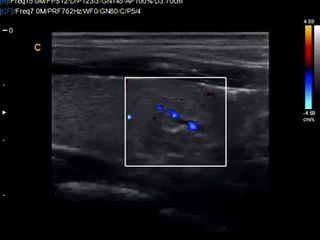

Q5 by Chison imaging Fetal Heart sonogram, easy to see heart in fetus, neonatal ultrasound